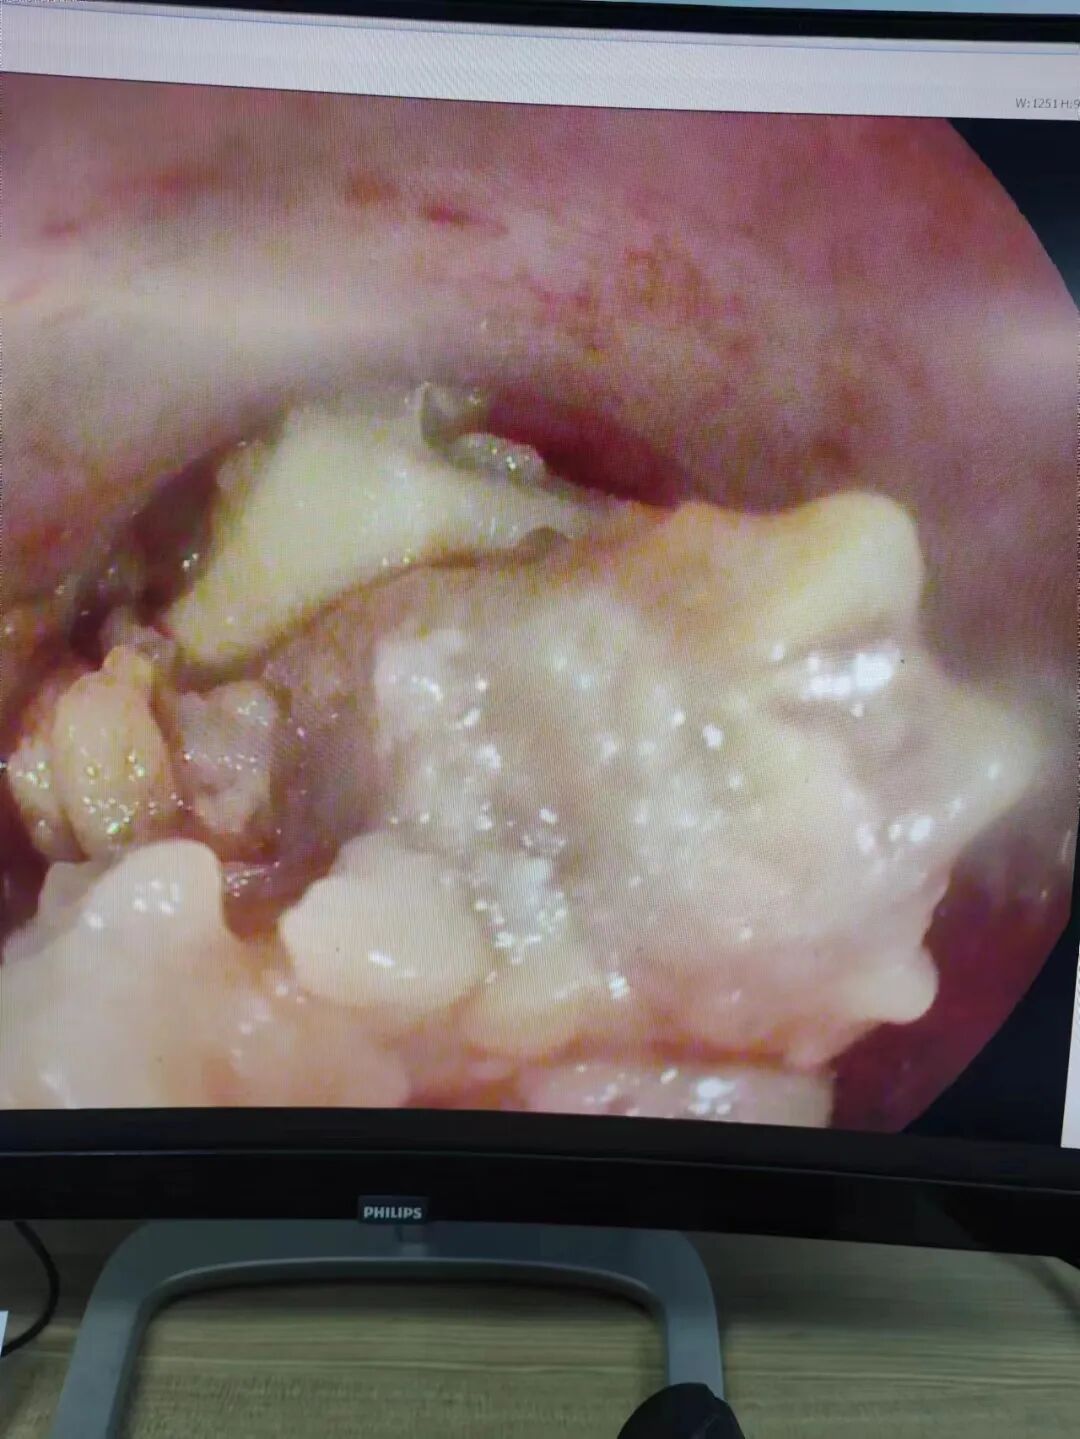

(內鏡下食管異物取出)

向總值班石院長請示后決定讓下夜班的尚明巖大夫從家里趕過來,檢查發(fā)現(xiàn)患者有房顫,屬于高風險患者。經研究后決定按原計劃進行。異物取出后,大家的心都放在肚子里。幸運的是,在取出之前異物沒有對身體造成更大的傷害,從病人來到醫(yī)院到異物取出不過1小時。